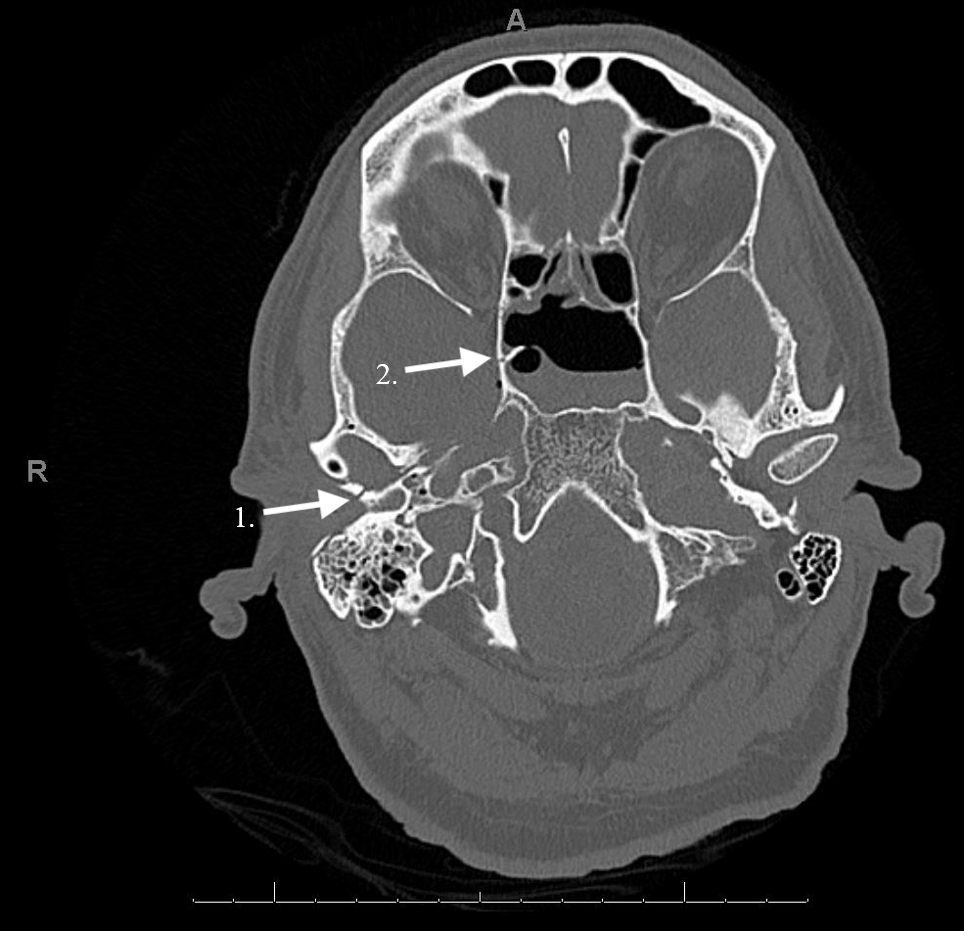

Osteomyelitis following an undisplaced basal skull fracture

Initial noncontrasted CT brain, showing the basilar skull fracture Basilar Skull Fracture Auto Racing an instantaneous basilar skull fracture causes the driver to suffer sudden death when the brainstem snaps loose. * at least 12 of the 15 drivers killed in major auto racing since 1991 died of injuries caused by violent motion of their. most basilar skull fractures occur in the setting of severe head traumas, such as those caused. Basilar Skull Fracture Auto Racing.

A 43yearold patient diagnosed with multiple basilar skull fracture Basilar Skull Fracture Auto Racing most basilar skull fractures occur in the setting of severe head traumas, such as those caused by motor vehicle. an instantaneous basilar skull fracture causes the driver to suffer sudden death when the brainstem snaps loose. * at least 12 of the 15 drivers killed in major auto racing since 1991 died of injuries caused by violent. Basilar Skull Fracture Auto Racing.